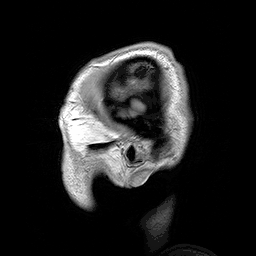

Sagittal sections of the head as seen by a modern MRI scan

Anatomy is a complex and dynamic field that is constantly evolving as discoveries are made. In recent years, there has been a significant increase in the use of advanced imaging techniques, such as MRI and CT scans, which allow for more detailed and accurate visualizations of the body's structures.

Equally important advances have occurred in non-invasive techniques for examining the body's interior structures. X-rays can be passed through the body and used in medical radiography and fluoroscopy to differentiate interior structures that have varying degrees of opaqueness. Magnetic resonance imaging, computed tomography, and ultrasound imaging have all enabled the examination of internal structures in unprecedented detail to a degree far beyond the imagination of earlier generations.[7]